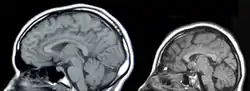

![]() مسوح عصبية لجمجمة شخص مصاب بصغر الرأس (إلى اليمين) وجمجمة شخص طبيعي (إلى اليسار) مسوح عصبية لجمجمة شخص مصاب بصغر الرأس (إلى اليمين) وجمجمة شخص طبيعي (إلى اليسار) | |